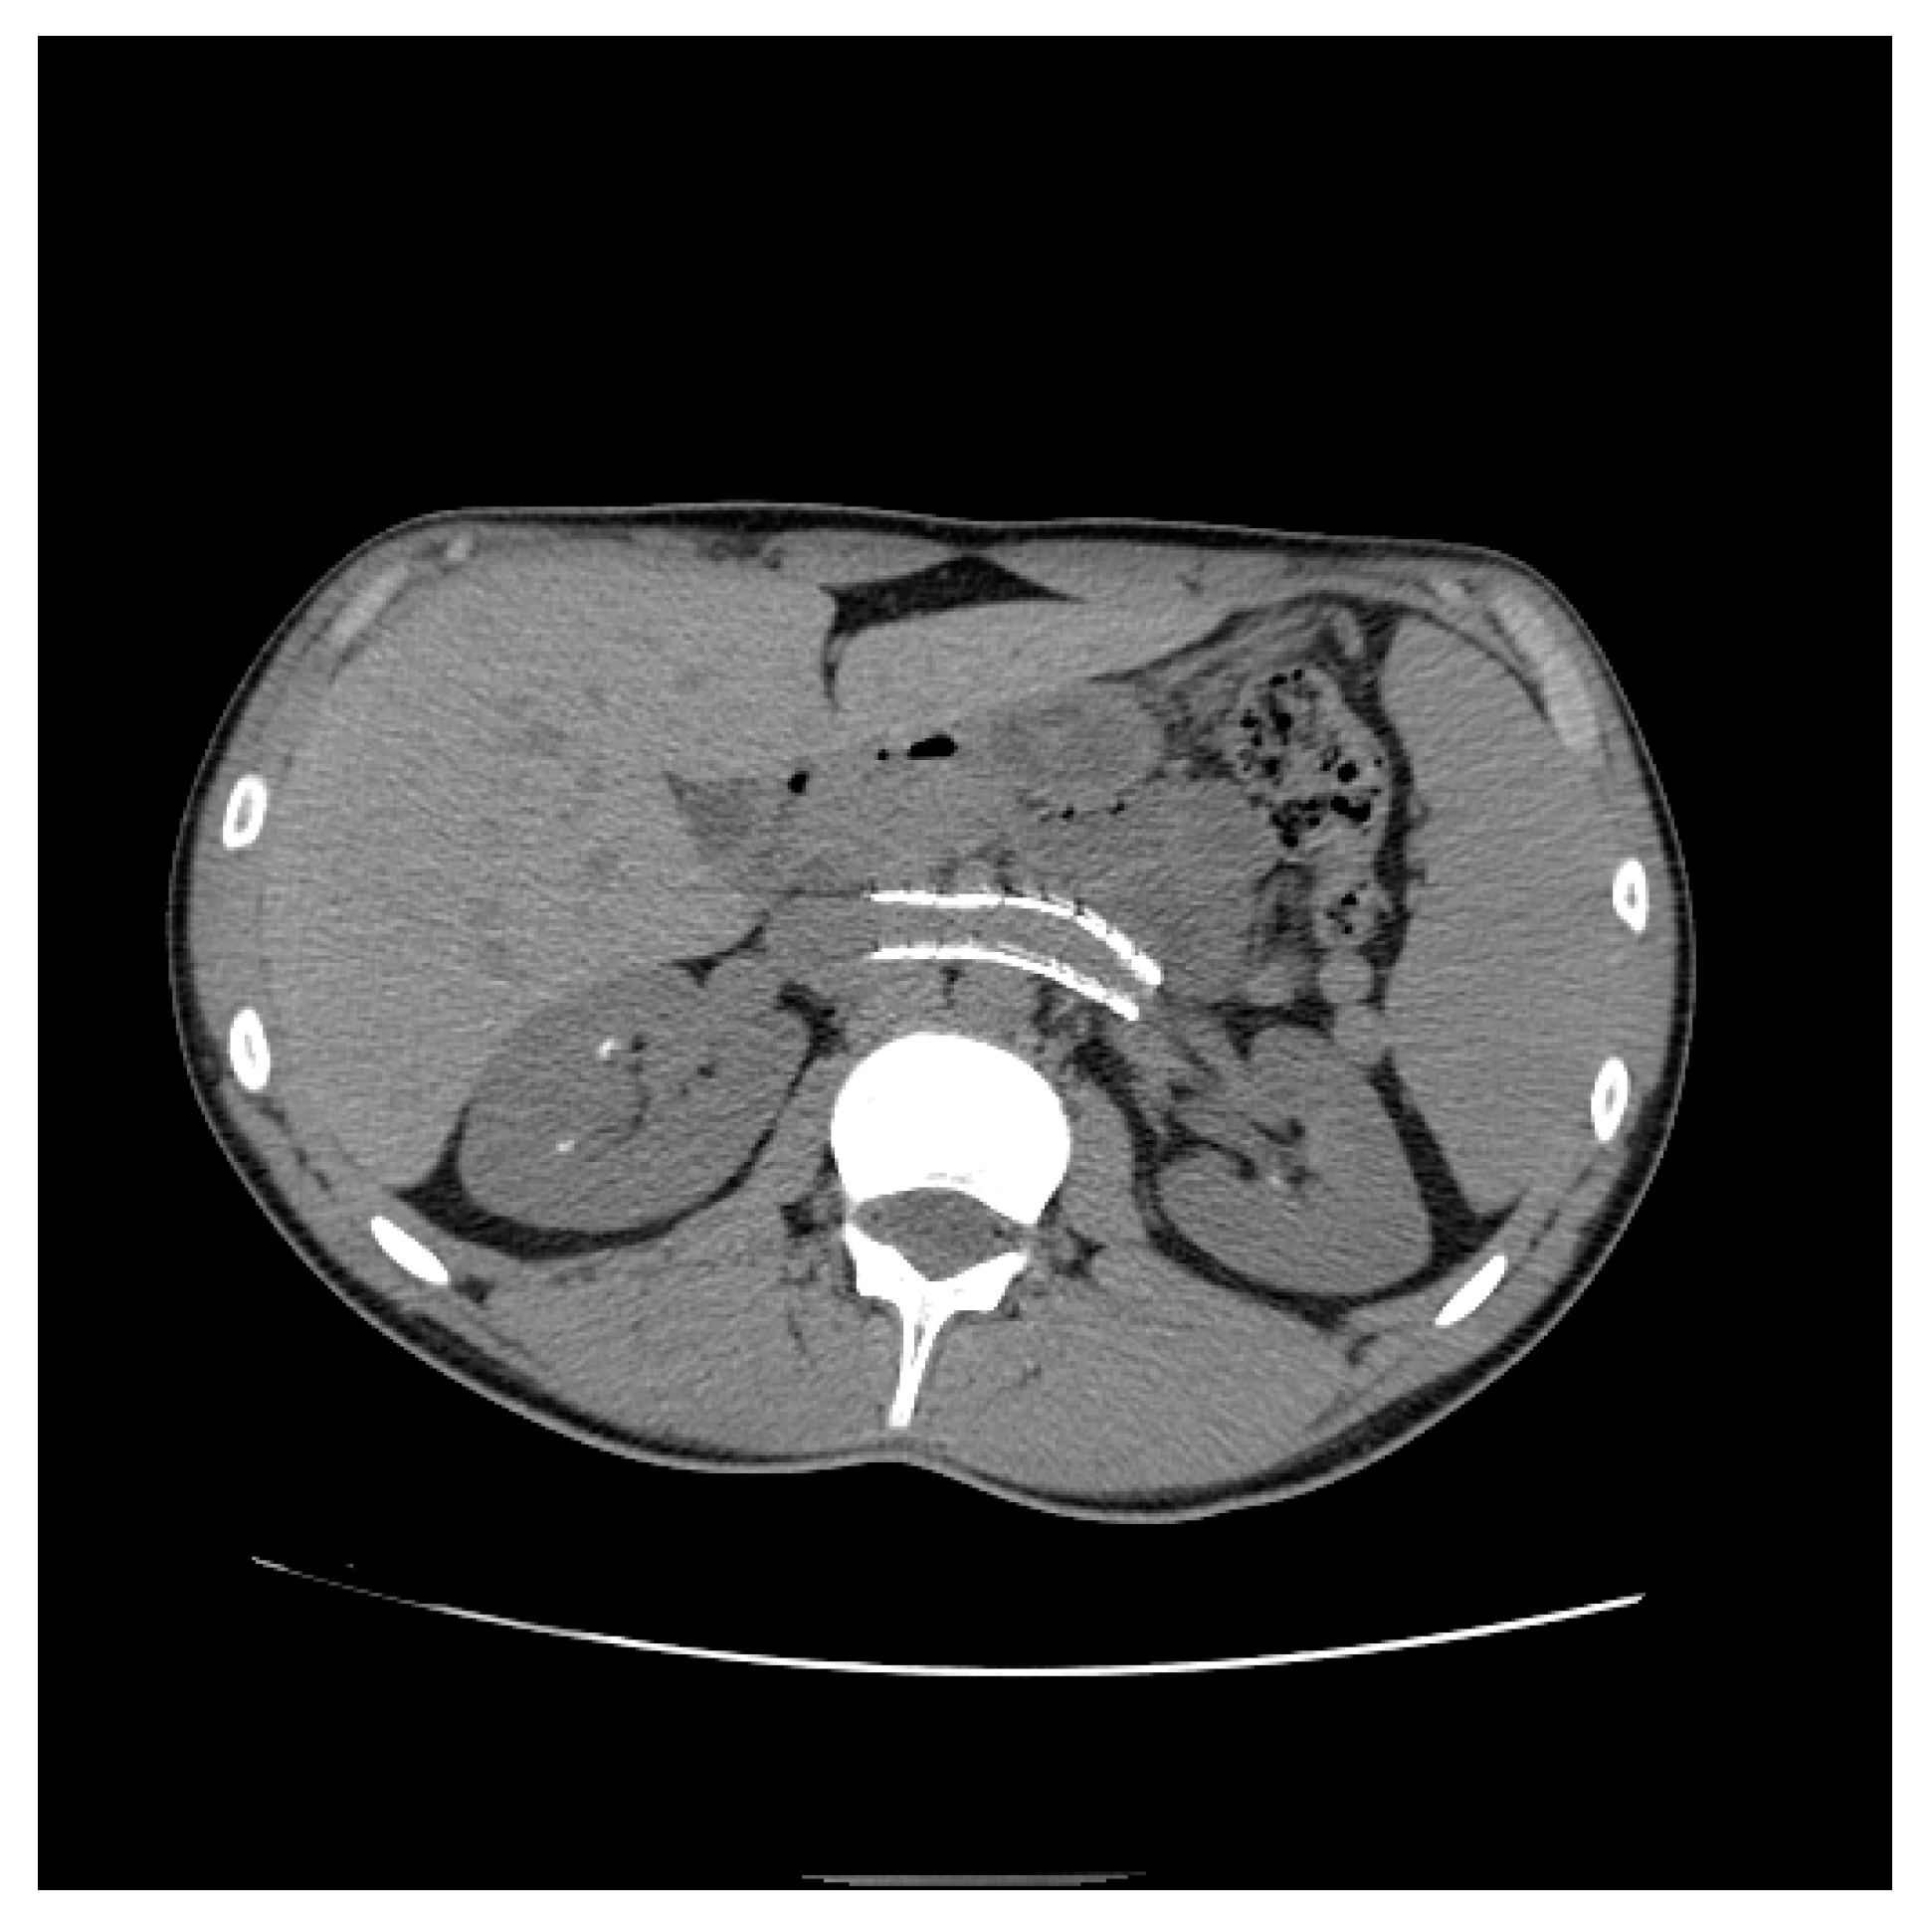

From Nutcracker Phenomenon to Nutcracker Syndrome: A Pictorial Review